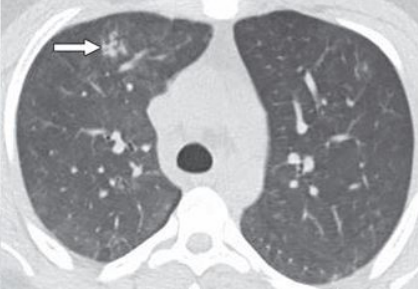

影像改变

患者胸部X线片可见渗出较前有所吸收(图3)

图3  患者影像学改善情况

上机后1周,于2020年10月17日成功撤离ECMO。复查胸部CT可见渗出实变影较前吸收,影像学改善(图4)

图片

图4  患者撤离ECMO后复查胸部CT